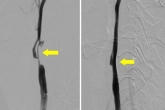

颈动脉狭窄是缺血性脑血管病的主要病因之一,多为动脉粥样硬化引起的。颈动脉支架具有微创、侵袭性小(无须开刀与全麻)、可重复进行、可同时处理多处病变等优点,是目前预防和治疗脑梗死的非常有效方法。颅内动脉狭窄也是中国人群常见的脑血管狭窄,特别是主干动脉大脑中动脉狭窄是脑梗死的重要原因,目前血管内介入治疗是解除颅内动脉狭窄的主要方法,相对颈动脉介入治疗,颅内动脉狭窄介入治疗要求相对较高,需要全身麻醉以及术者的严格评估、围手术期管理,较超的介入技术,丰富的临床经验。短暂性脑缺血发作(TIA)是一种反复发作的局部脑供血障碍导致的短暂性神经功能缺失,主要表现为一过性黑朦、失语或言语不清、运动障碍、感觉障碍等,50%的缺血性卒中患者在卒中前有TIA史。因此短暂性脑缺血发作是脑梗死

缺血性卒中具有较高的发病率,以美国为例每年发生80万例卒中,其中新发卒中61万例,缺血性卒中占87%。大血管闭塞(指颈内动脉、大脑中动脉主干、基底动脉和颅内椎动脉)在缺血性卒中占有较高的比例。近年来,多项大型随机对照研究证实了急性前循环大血管闭塞血管内治疗的有效性,与单纯静脉溶栓相比实现了较高的再通率和较低的致残、致死率,已成为急性缺血性卒中的主要治疗方式之一。然而,血管再通手术不同于传统手术,其再通时间对于手术效果至关重要。早期恢复脑血流是防止脑组织永久性损害的关键,再通时间与预后密切相关,快速再通技术对于接受血管内治疗的卒中患者具有重要意义。